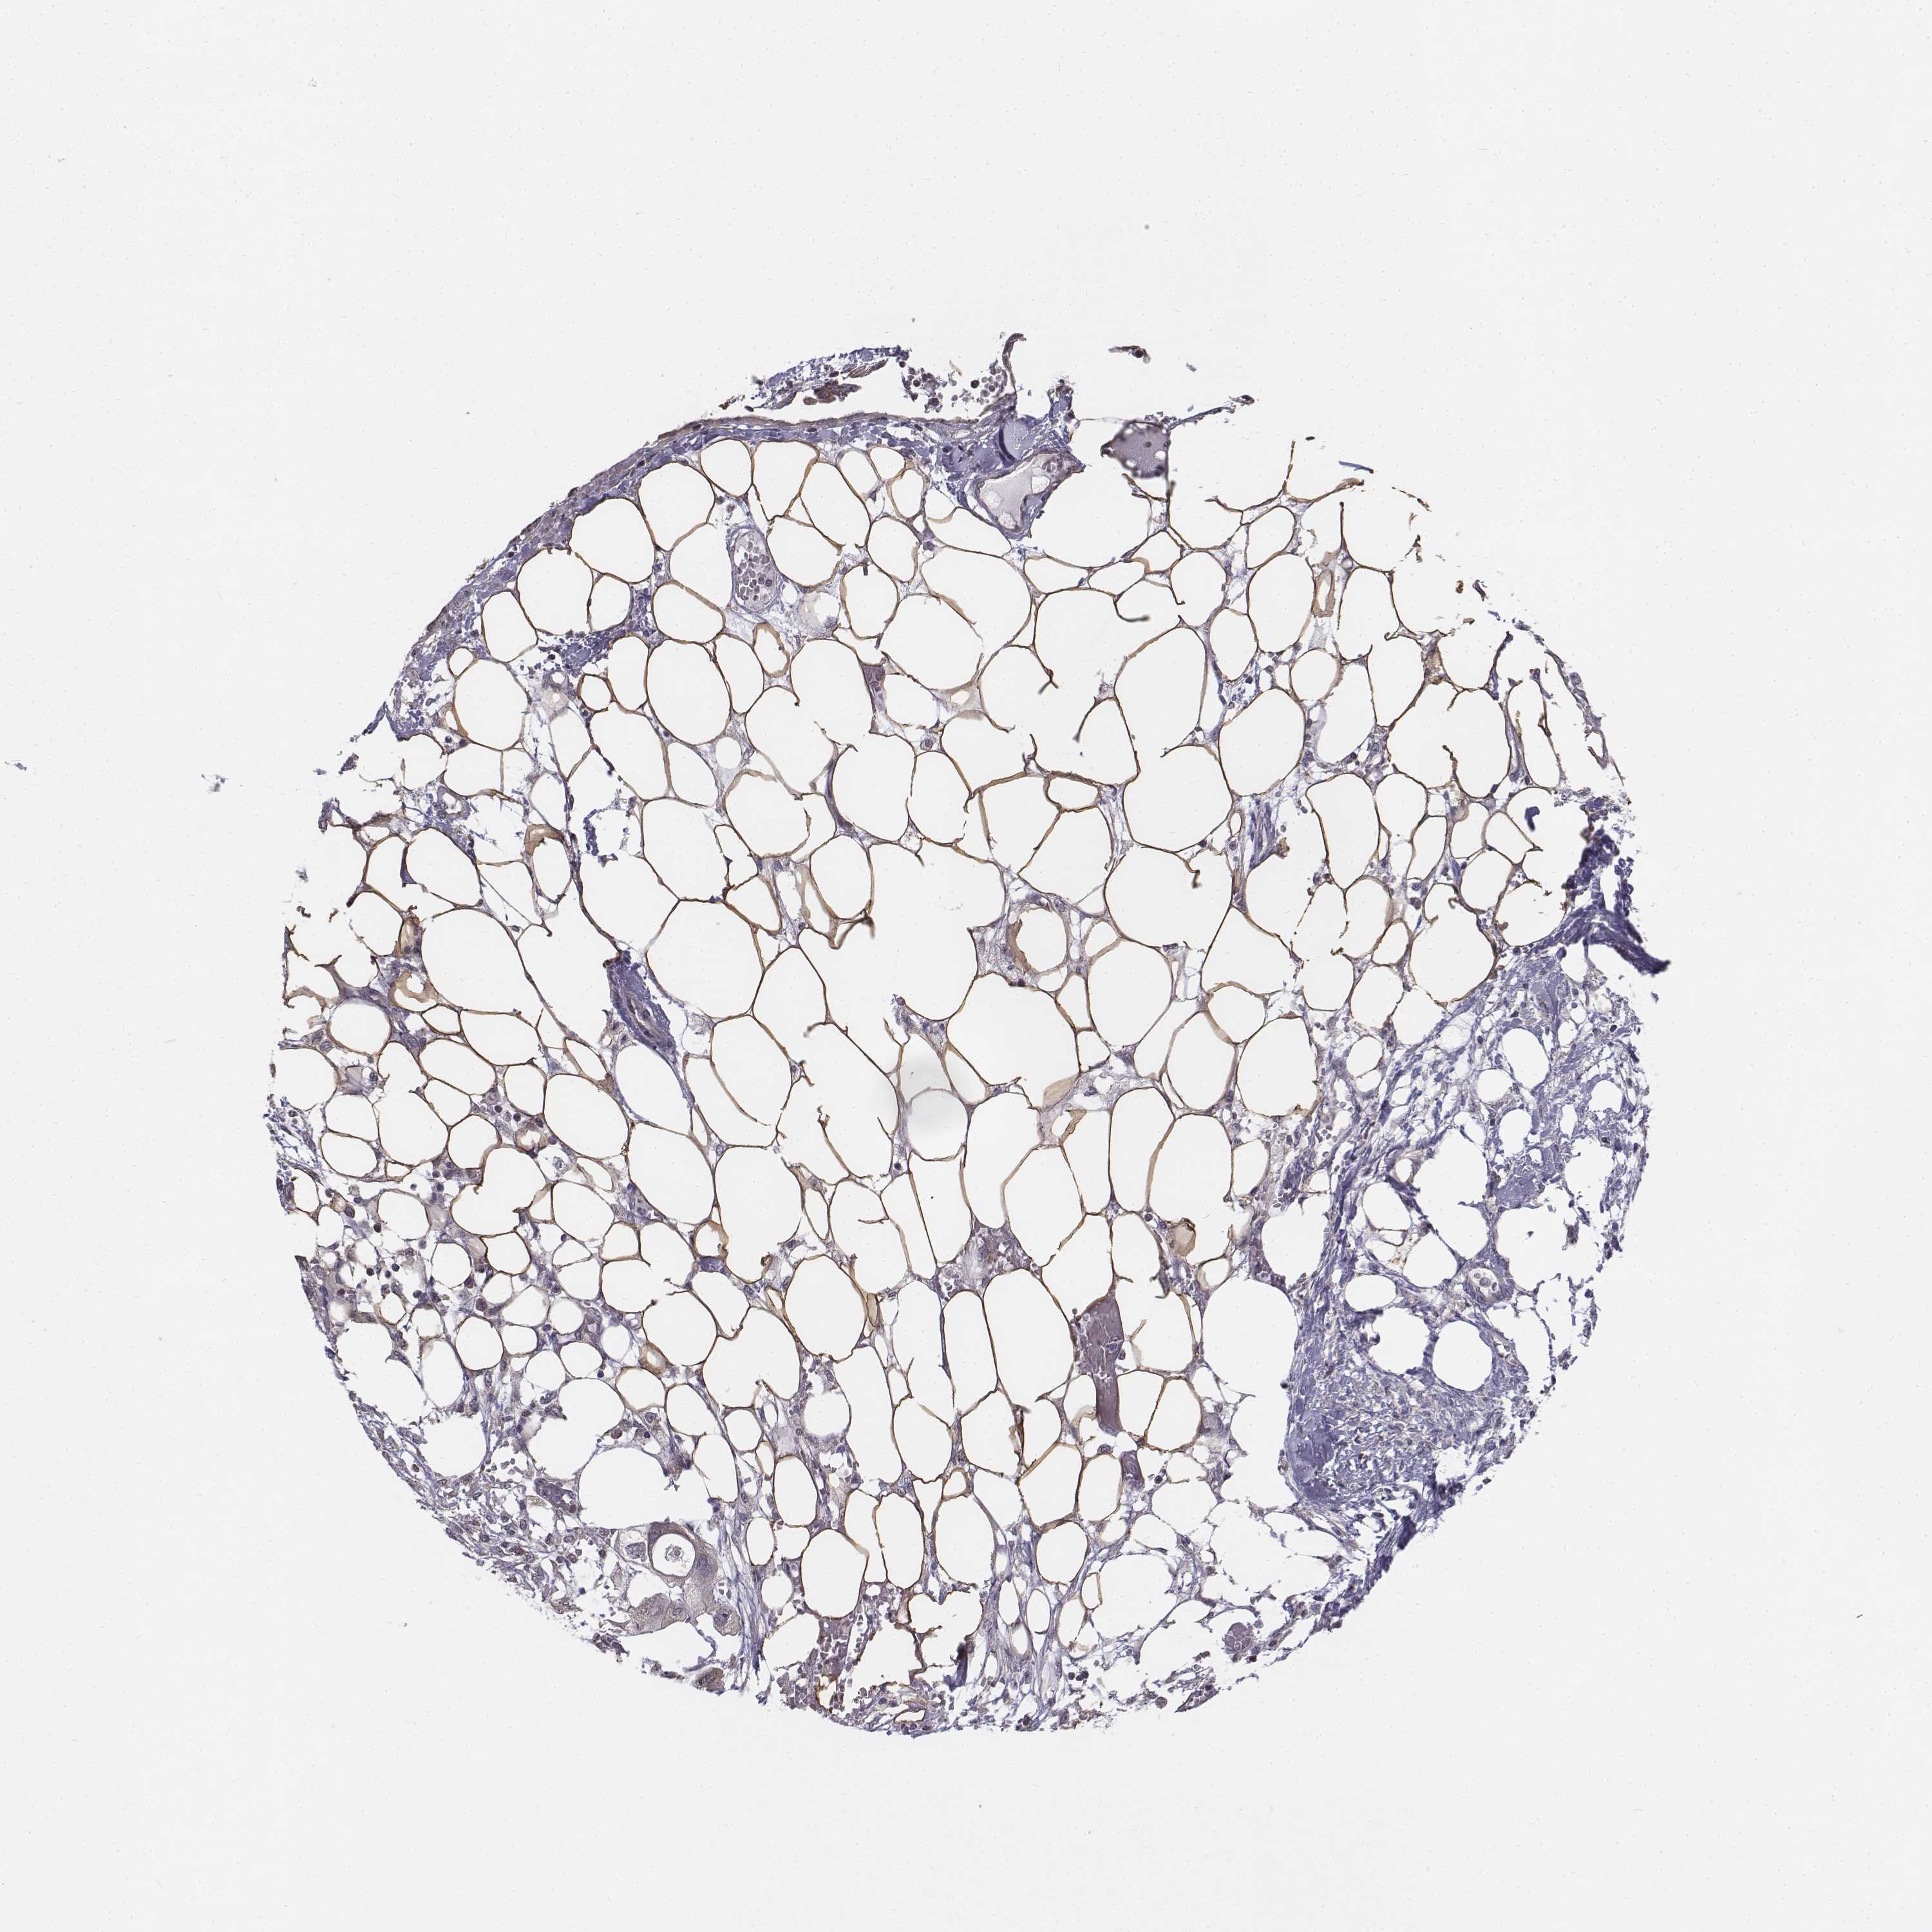

ENDOMETRIAL CANCER - Protein expressioni

A mouse-over function shows sample information and annotation data. Click on an image to view it in a full screen mode. Samples can be filtered based on level of antibody staining by selecting one or several of the following categories: high, medium, low and not detected. The assay and annotation is described here.

Note that samples used for immunohistochemistry by the Human Protein Atlas do not correspond to samples in the TCGA dataset.

Antibody stainingi

Antibody staining in the annotated cell types in the current human tissue is reported as not detected, low, medium, or high, based on conventional immunohistochemistry profiling in selected tissues. This score is based on the combination of the staining intensity and fraction of stained cells.

Each image is clickable and will lead to virtual microscopy that enables deeper exploration of all samples and also displays staining intensity scores, fraction scores and subcellular localization as well as patient and tissue information for each sample.

Antibody HPA013138

Antibody CAB016390

Staining

High

Medium

Low

Not detected

Intensity

Strong

Moderate

Weak

Negative

Quantity

>75%

75%-25%

<25%

None

Location

Nuclear

Cytoplasmic/membranous

Cytoplasmic/membranous,nuclear

Adenocarcinoma, NOS

Adenocarcinoma, metastatic, NOS